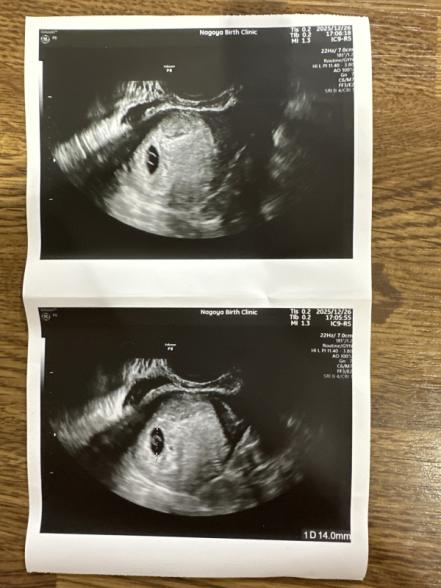

最終月経開始日は11月12にちで排卵日はわからないですが、11月27日に病院行った時には排卵確認できました。その時には排卵してから2.3日経ってる感じかな〜と言われ24.25.26.27と曖昧な感じです。その後12月11日に妊娠検査薬したところ陽性反応でて12月15日にA院に受診。まだ小さくて胎嚢はほぼ見えずこれかな?ぐらいの物しか確認できずその時に4週5日と言われました。27日から年末休みに入るから26日だとギリギリ心拍みえるかわからないけどまあ来てとゆう感じでおわりました。その後19日にB院に受診したところ胎嚢が4ミリの大きさで確認でき5週2日かなと思いきや、4周ぐらいだねーと言われその時にA院と週数と恐らくの出産予定日に1週間の差がありん?どっちが本当?と違和感が少しありましたが検索したところ心拍確認まではそおゆう事はあるあるだと書かれてたのに気にしませんでした。妊娠発覚後眠気だけはありましたがつわりがなく軽いタイプなのかと喜んでましたが月曜日ぐらいから眠気も前に比べたらそんなになくなりつわりもないし大丈夫なのか不安になってきました。そして今日の12月26日A院に行ったら今日は7週と2日と言われこの週数にしては胎嚢も小さいし胎芽も心拍も確認できない。卵黄嚢が4.4ミリで3.5ミリ以上だとダメな事が多い言われました。しばらくしたら出血してきてそのまま終わるかもしれないし年明けの1月7日にまた来て出血なければまた内心エコーみますとゆうほぼせっかく妊娠したけど残念ですとハッキリ流産みたいな感じで言われました。

でもB院と週数も違うしすがる想いで同日の26日の午後にB院に行きました。B院では胎嚢は14ミリで確かに心拍も胎芽も確認できないが11月12日が最終月経開始日なら今日は6週2日だと。元々排卵障害があり生理周期が不規則で50日とかの時もあるので私の場合医者が元にしてるのは正常の方の28日周期の方を元にして伝えてるのであなたの場合不規則だからズレてる事もありえるし今日の今日で流産とゆう確定はしずらいと言われました。A院で言われた卵黄嚢4.4は大きいと言われたのもB院では気にならない大きさだと言われました。不安なら4日後30日に6週6日だから微妙で今日と変わらず見えないかもだし30日に見えなくてもまだ流産と確定できないけど来ていいよと言ってくださり、年明けの1月5日だと確実に診断できるよと言われました。B院はまだ希望ある感じでA院はほぼダメみたいな感じで言ってる事が違うのとA院は不妊治療専門だからそっちの意見のが正しいのかな?と思ったり不安です。生理周期が不規則ですが今回は妊活もしてたので基礎体温も毎日測り27日の時点では確実に排卵できてるのを確認できてるので何日かは未定ですがそこまで範囲しぼれててもこんなに院によって週数変わったりするのでしょうか?他の先生方の意見ともうほぼダメな状態なのかまたどう1月5日まで過ごしたらいいのか知りたいです。出血はなくなんとなく激しい腹痛とかないですが軽い鈍痛と腰痛(生理痛の時のような鈍い感じ)が今日なんとなく感じるかもと思いました。でも内心エコーしたから刺激されたのかなとかネットでは子宮が大きくなってきてると書かれてたりこれだけでは流産とは限らないと書いてあったのでそれも踏まえて意見が欲しいです。長くなりましたがよろしくお願いします。